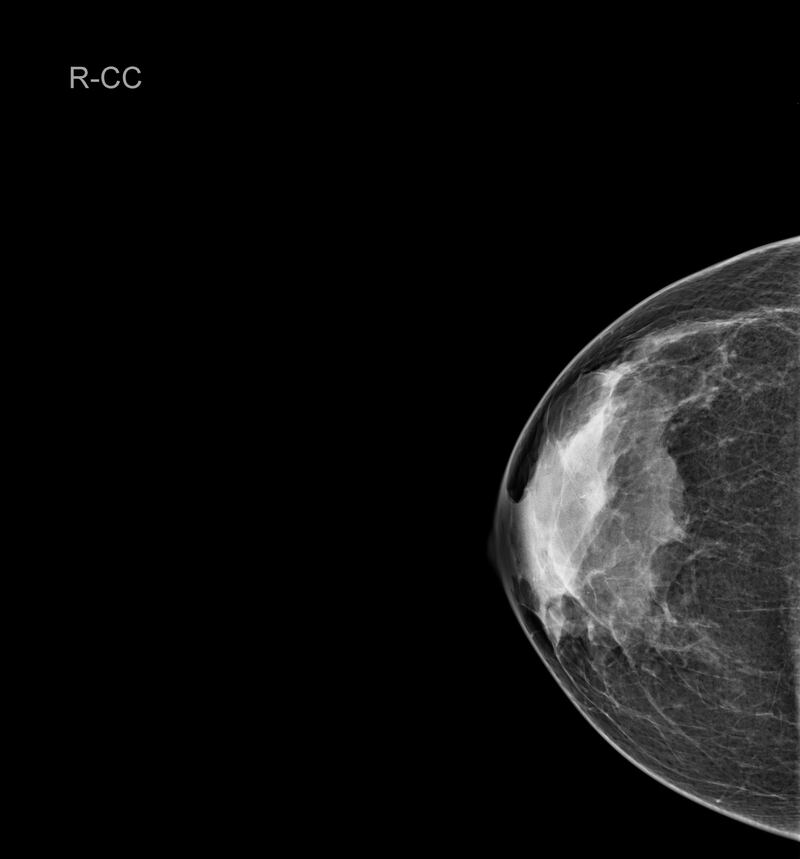

¿Qué es una mamografía?

“Una mamografía es una imagen de la mama tomada con rayos X que permite ver una imagen del interior de los senos. Existen mamografías de detección y mamografías de diagnóstico. Al realizarse una mamografía como especialista puedo detectar irregularidades en la mama o tumores que aún no se pueden sentir”, cuenta Clayreth Vinueza especialista en radiología.

Para la experta una mamografía debe realizarse a partir de los 40 años una vez todos los años. Además, que en mujeres con antecedentes de cáncer de mama o de varios se recomienda comenzar antes.